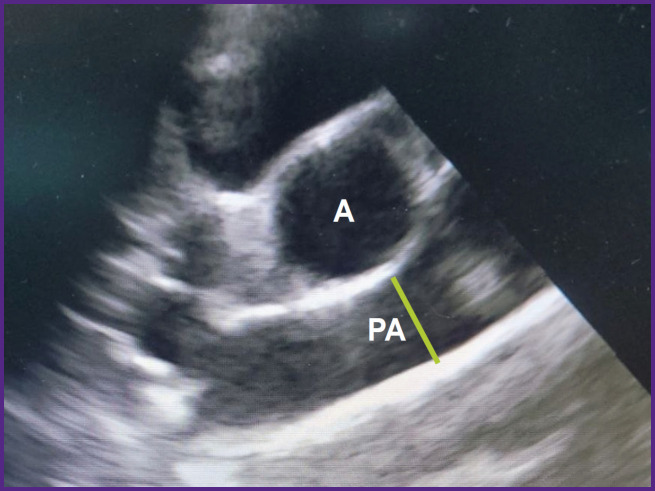

Materials and methods: The study was performed on 17 healthy crossbred Romanov sheep weighing 20-29 kg in group 1 (n=7) and 30-43 kg in group 2 (n=10). All animals underwent echocardiography examination on the Philips CX-50 apparatus (revision 3.1.2; Philips, Netherlands) with a sector-phased S5-1 sensor from the right parasternal projection (long and short axis) to determine the heart rate, right ventricular wall thickness in diastole, right and left ventricular end-diastolic dimensions (RV EDD and LV EDD), left ventricular end-systolic dimension (LV ESD), interventricular septum (IVS) thickness in systole and diastole, left ventricular posterior wall thickness in systole and diastole.Functional parameters of the left ventricle (left ventricle end-systolic and end-diastolic volumes (LV ESV and LV EDV), ejection fraction and shortening fraction) were calculated using the modified Simpson method built into the echocardiography software. The diameter of the mitral annulus and the characteristics of the aortic root were also measured: the diameters of the aortic valve, Valsalva sinuses, and sinotubular junction, as well as the height of the aortic root from the fibrous ring to the line of the sinotubular junction. Direct measurements of the ascending aorta and pulmonary artery diameters, intercommissural distances, and the height of the aortic valve leaflets were performed after autopsy.

Results: A number of anatomical and functional parameters of the sheep heart such as ejection fraction, myocardium thickness, LV EDD and LV ESD, aorta, and pulmonary artery diameters, have been established to be close to those of the human heart. At the same time, LV EDV and LV ESV of the sheep are significantly lower than in humans, even in relation to the body surface area, and the average mitral valve diameter is larger. Despite the same diameters of the aortic valve, Valsalva sinuses, and sinotubular junction, the structures of the ovine and human aortic roots are different: the sheep root features a smaller height and intercommissural distances of the cusps. In addition, some differences were found in the arrangement of the cusps in relation to the valve axis: the intercommissural distance of the right coronary leaflet was almost 2 times greater than the similar indicator of the left coronary leaflet.Most anatomical and functional parameters have not shown any correlation with the animals' body weight. Only in group 2, a significant positive correlation between body weight and the height of the aortic valve leaflets was found.